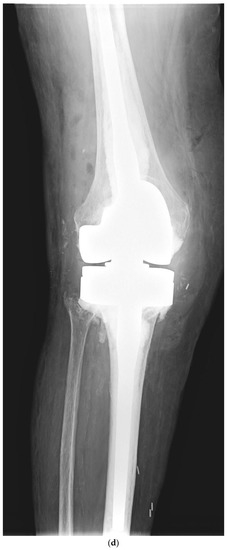

Although one-stage revision TKA is performed in certain situations and centers, a PJI usually requires a two-stage revision TKA, which involves a double surgical intervention. First, the removal of the infected implant (septic loosening) is required. Following this procedure, a period of several weeks of antibiotic treatment is needed until the infection is considered cured (normalization of the ESR and CRP and healing of the surgical wound). The second intervention is the insertion of a new implant, using a model that is stable for proper functioning of the knee [11]. Figure 1 shows a case of PJI (septic loosening) that was solved by a two-stage revision TKA.

Figure 1. (ad). Periprosthetic joint infection of a primary total knee arthroplasty (TKA) that was resolved by a two-stage revision TKA: (a) preoperative anteroposterior (AP) radiograph; (b) preoperative lateral image; (c) postoperative AP radiograph showing the prosthesis implanted in the second-stage revision (rotational hinge design); (d) lateral image of the aforementioned prosthesis.